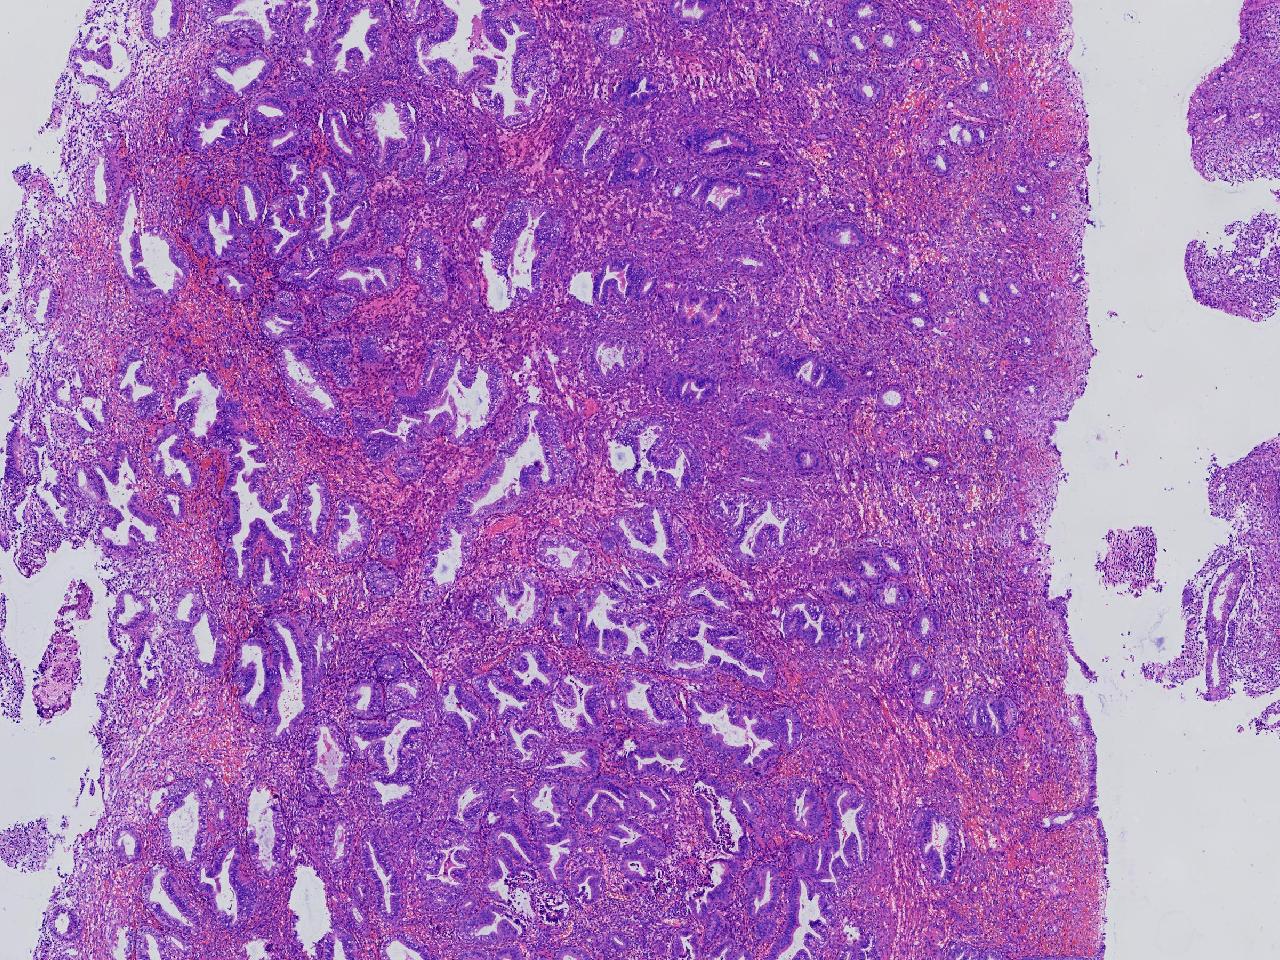

请教。1.有没有非典? 2.内膜是什么变化?

女,50岁,彩超示:粘膜厚度1.1cm。宫腔可见数个高回声,提示宫腔息肉。

子宫内膜+内膜息肉

灰粉色不整形软组织多块,3X3X2厘米。

子宫内膜息肉。

没有非典。

无非典型性子宫内膜增生,子宫内膜息肉

无非典内膜伴息肉。